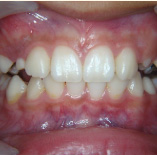

セラミック治療

こんな歯並びでもご心配なく。矯正という方法をとらなくても、ここまできれいに治せるんです。見た目だけでなく歯ブラシもやり易くなりました。笑顔に自信がつきますよ。

- 施術前

- 施術後